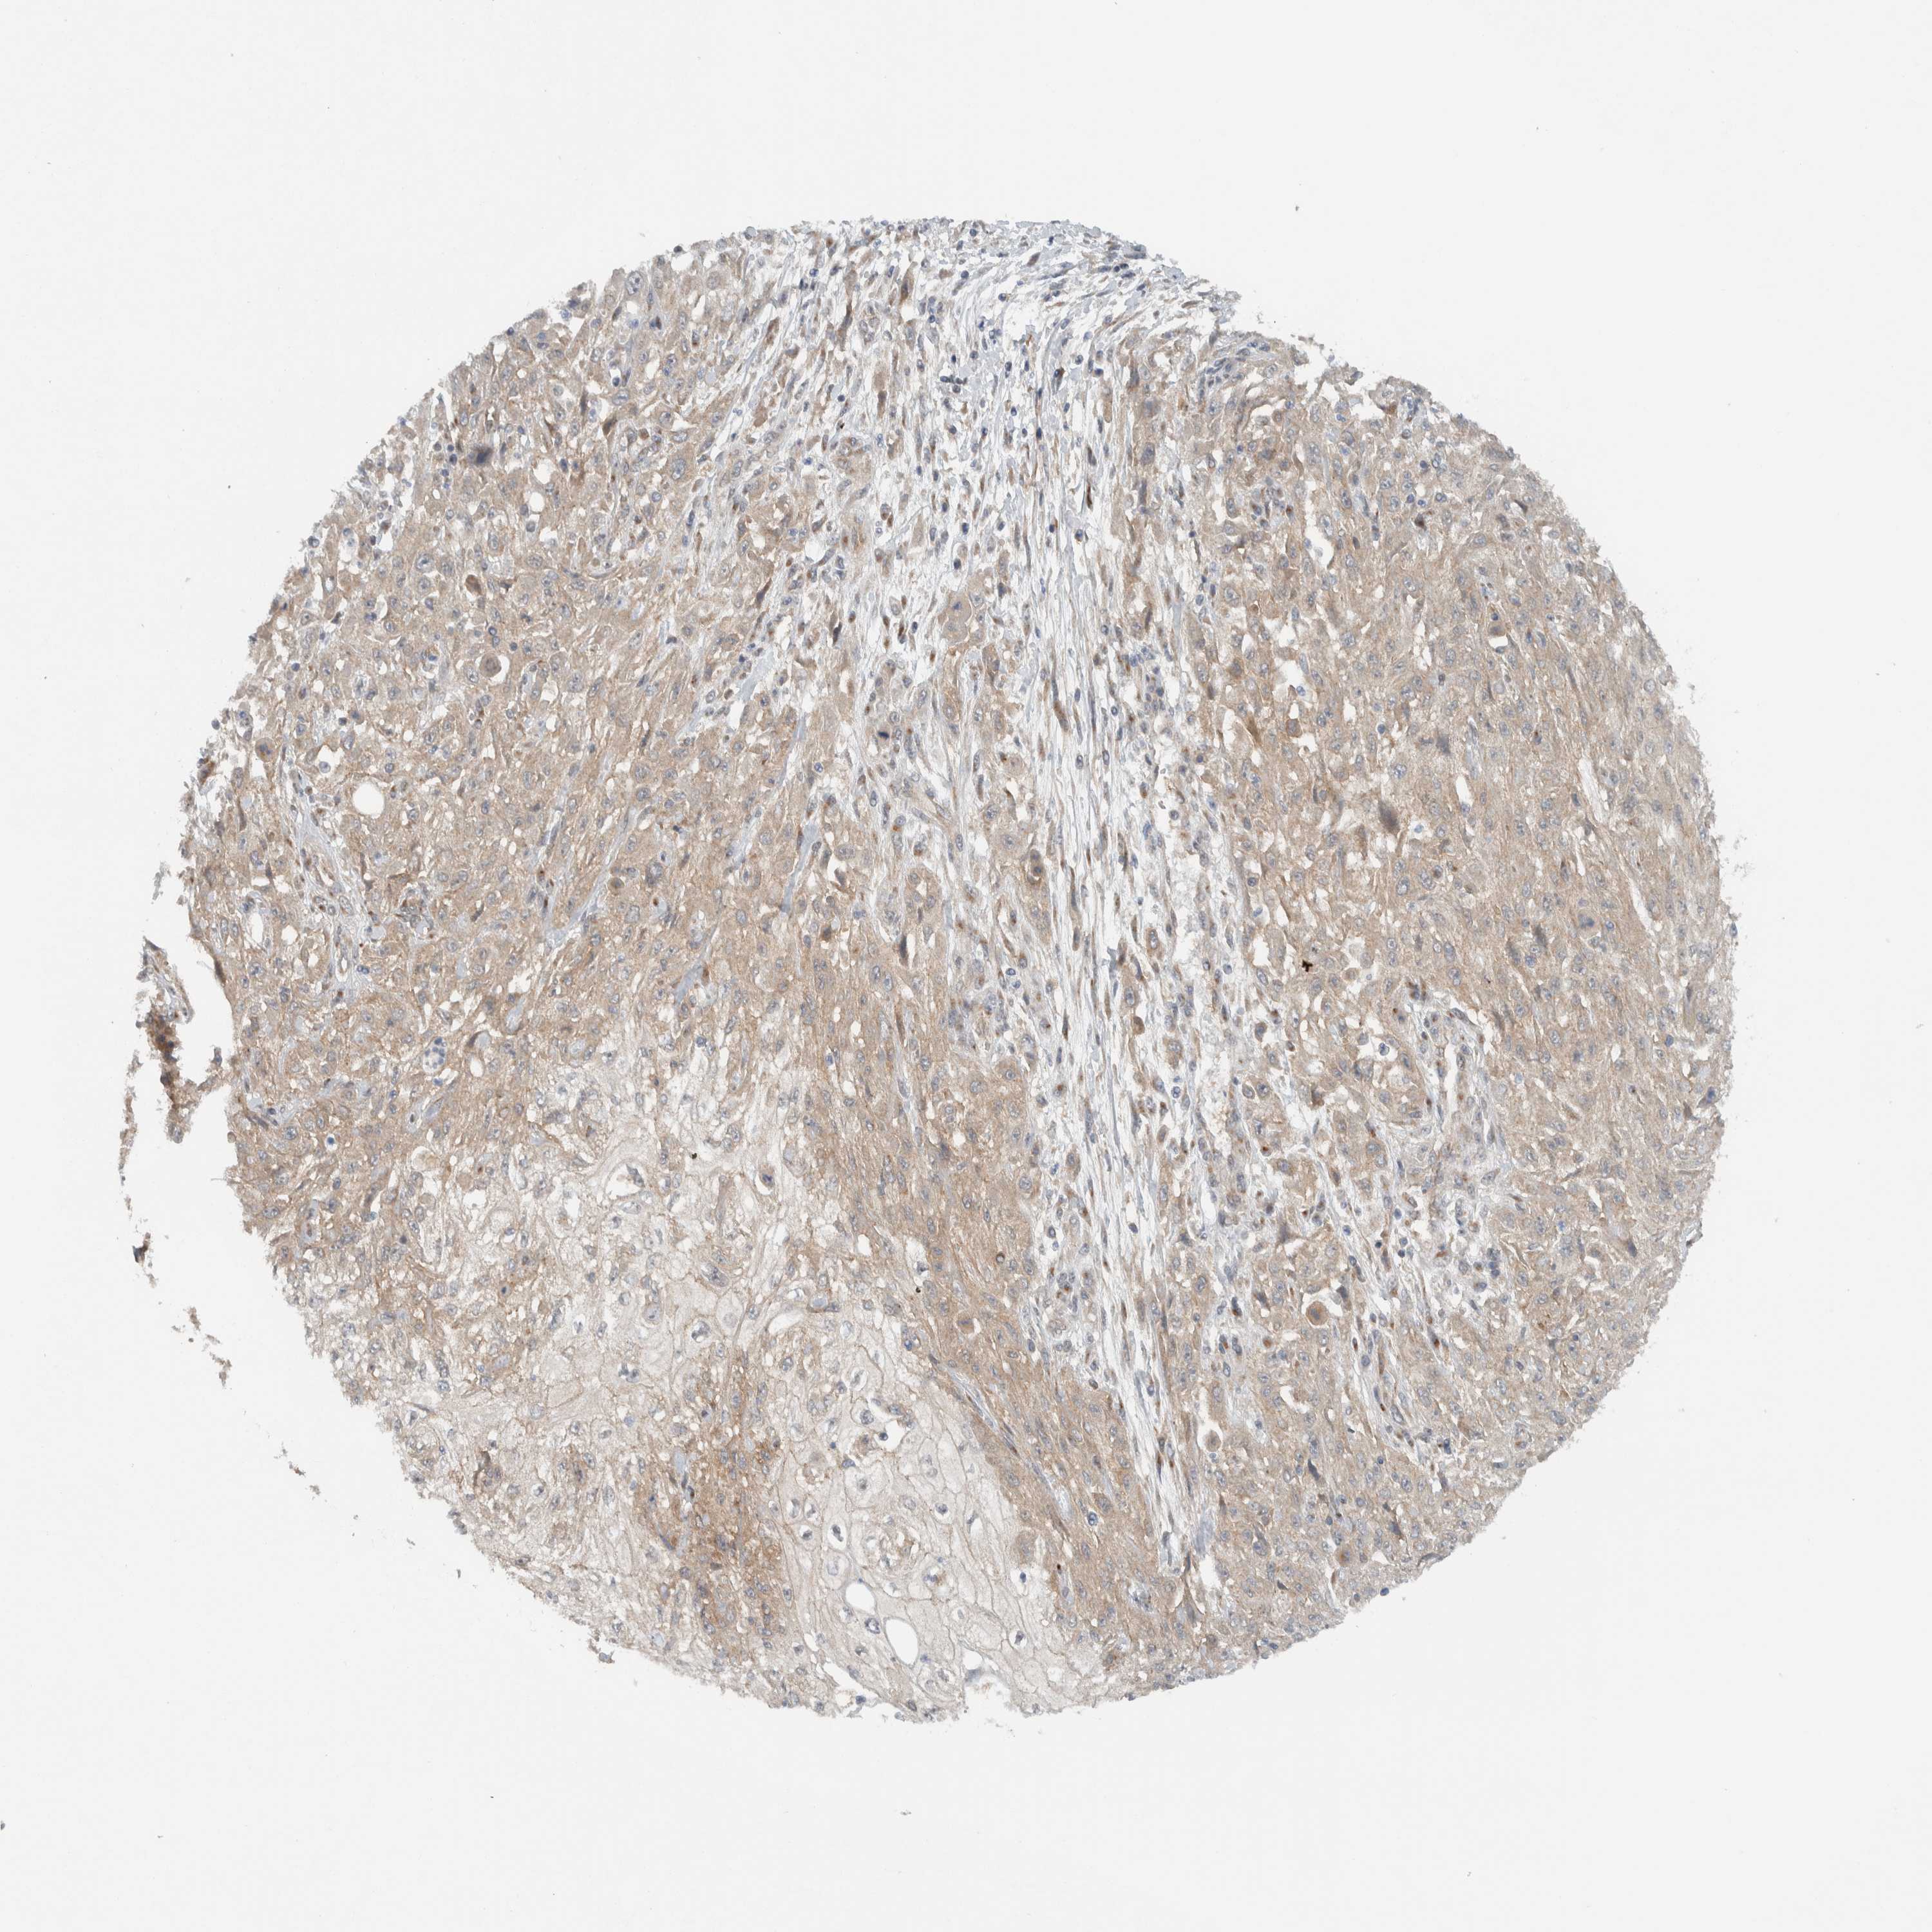

Basal cell and squamous cell cancer

SKIN CANCER - Protein expressioni

A mouse-over function shows sample information and annotation data. Click on an image to view it in a full screen mode. Samples can be filtered based on level of antibody staining by selecting one or several of the following categories: high, medium, low and not detected. The assay and annotation is described here.

Antibody stainingi

Antibody staining in the annotated cell types in the current human tissue is reported as not detected, low, medium, or high, based on conventional immunohistochemistry profiling in selected tissues. This score is based on the combination of the staining intensity and fraction of stained cells.

Each image is clickable and will lead to virtual microscopy that enables deeper exploration of all samples and also displays staining intensity scores, fraction scores and subcellular localization as well as patient and tissue information for each sample.

Antibody HPA024093

Staining

High

Medium

Low

Not detected

Intensity

Strong

Moderate

Weak

Negative

Quantity

>75%

75%-25%

<25%

None

Location

Nuclear

Cytoplasmic/membranous

Cytoplasmic/membranous,nuclear

Squamous cell carcinoma, NOS